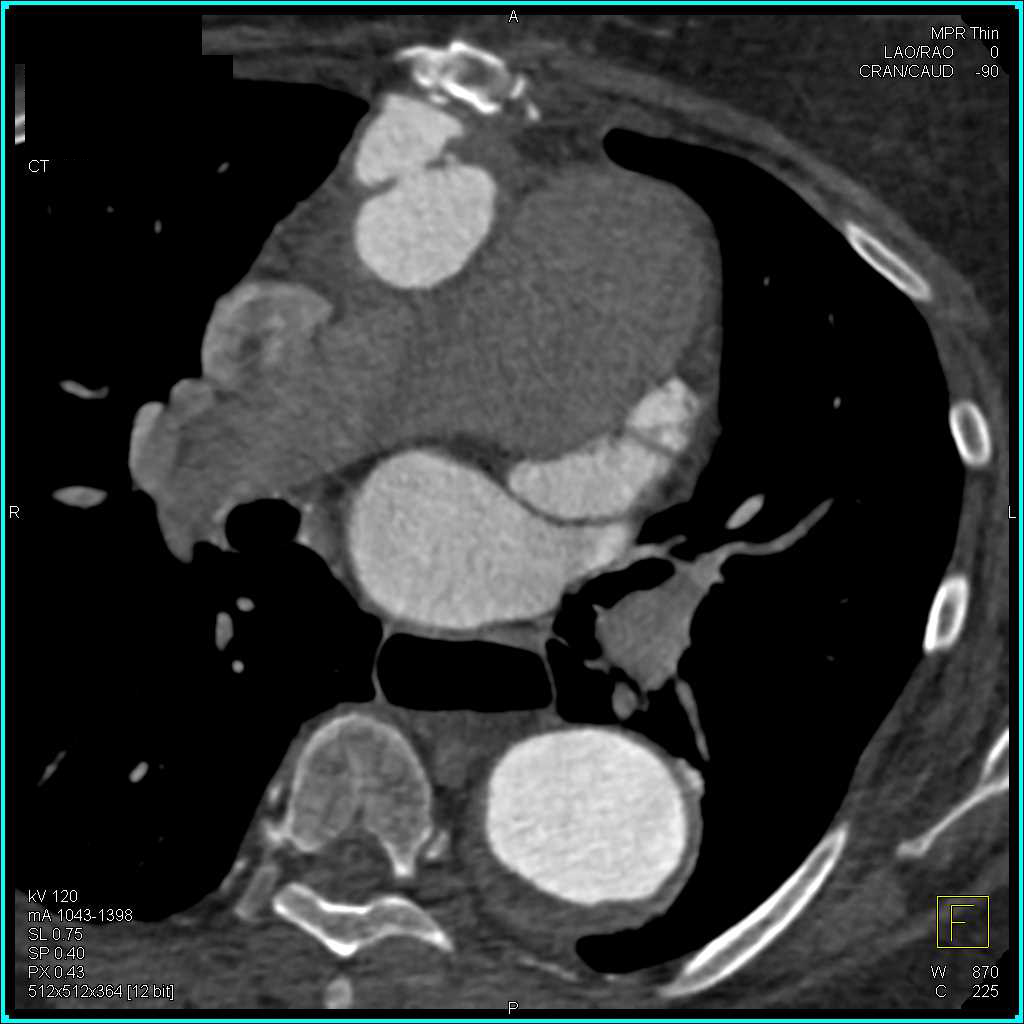

Superior Mesenteric Artery (SMA) Occlusion with Ischemic Bowel and Midgut Volvulus and Thrombus in Left Atrial Appendage